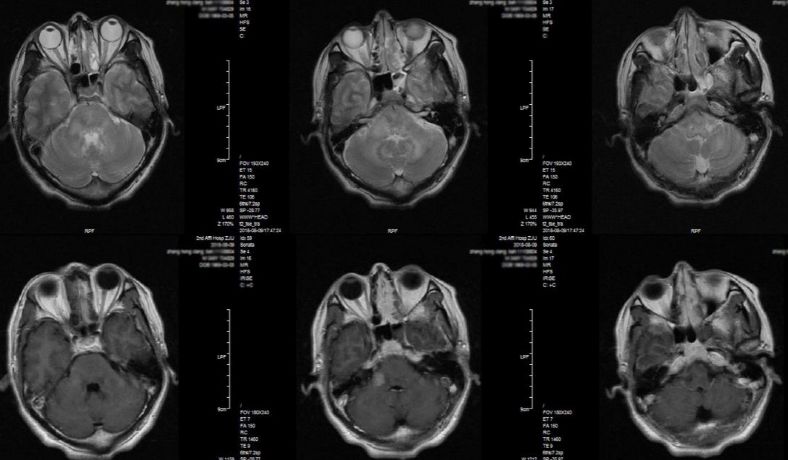

患者3月前发热后出现行走不稳,走路摇晃,伴口齿不利,偶有饮水呛咳,间歇发热,具体体温不详。 2月前症状逐渐加重,至外院就诊,头颅增强MRI:延髓、桥脑、中脑和桥小脑臂异常信号。诊断为“颅内多发病灶(脑干、小脑),代谢、炎症首先考虑,肿瘤不排除”(图1),入院后脑脊液检查:蛋白72.7mg/dL,有核细胞10/ul,墨汁染色及抗酸杆菌染色阴性。予呋喃硫铵、弥可保营养神经治疗,症状稍好转后出院,但仍间断发热。近1月来病情复发加重,来浙医二院就诊,头部增强磁共振显示脑干多发强化灶(图2)。为明确病因来浙医二院行立体定向活检术。门诊以“颅内多发病灶,性质待查”收住院。

图1. 外院MRI检查,提示颅内多发病灶(脑干、小脑),代谢、炎症首先考虑,肿瘤不排除。